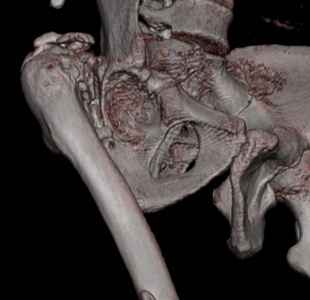

Уважаемые коллеги. Пациент 30 лет 3 года назад в результате травмы получил травматический дефект нижних конечностей до в/3 голеней, был пропущен вывих бедра.

В настоящее время очень неплохо ходит на протезах, движения в неоартрозе близки по объему к здоровой стороне. Основная жалоба - выраженная боль при ходьбе. планируем двухэтапное эндопротезирование - задним доступом мобилизовать проксимальный отдел бедра, резецировать шейку, аппаратом низвести бедро(головку оставить там где она есть, так как больших дефектов не видно(может пригодится в последующем?)). Вторым этапом бесцементное эндопротезирование. Насколько такой вариант реалистичен? Доступ для второго этапа? Может быть другие варианты?С уважением, Максим

На последнем срезе КТ задний край практически отсутсвует по сравнения со здоровой стороной. Разумеется, что это плоскостное изображение, но головка вывихнулась не только в плоскостную щель захваченную на КТ. Если вы считаете, что удастся установить туда чашку даже низкопрофильную, остается пожелать вам успехов. Но перед этим можно смоделировать установку чашки на скиаграммах КТ.

За пожелание успехов - спасибо, думаю это пригодится, не очень понял про плоскостную щель, специально предоставил срезы на уровне свода - он цел, дефект заднего края ниже, за счет заглубления он будет еще меньше, по данным 3d - должно получиться.

Низводить надо обязательно, лучше в аппарате и лучше без остеотомии.

Решение по ВВ придется принимать по месту.... Сумеете "подрыться" и получить хорошее покрытие чашки (+2 винта об-но) - хорошо, если нет -

костная аутопластика из головки.